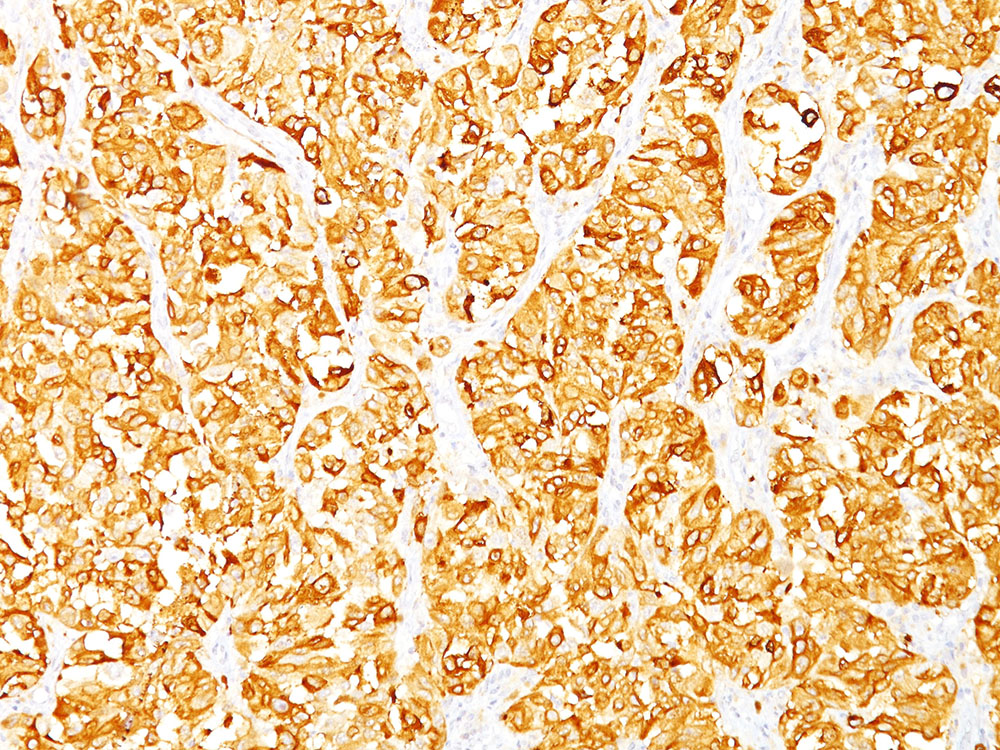

Formalin-fixed, paraffin-embedded human melanoma stained withMelan-A MAb (DT101+BC199). Note cytoplasmic staining of cells. |

This antibody recognizes a protein doublet of 20-22kDa, identified as MART-1 (Melanoma Antigen Recognized by T cells 1) or Melan-A. MART-1 is a newly identified melanocyte differentiation antigen recognized by autologous cytotoxic T lymphocytes. Seven other melanoma associated antigens recognized by autologous cytotoxic T cells include MAGE-1, MAGE-3, tyrosinase, gp100, gp75, BAGE-1, and GAGE-1. Subcellular fractionation shows that MART-1 is present in melanosomes and endoplasmic reticulum. This MAb labels melanomas and other tumors showing melanocytic differentiation. It is also a useful positive-marker for angiomyolipomas. It does not stain tumor cells of epithelial, lymphoid, glial, or mesenchymal origin.